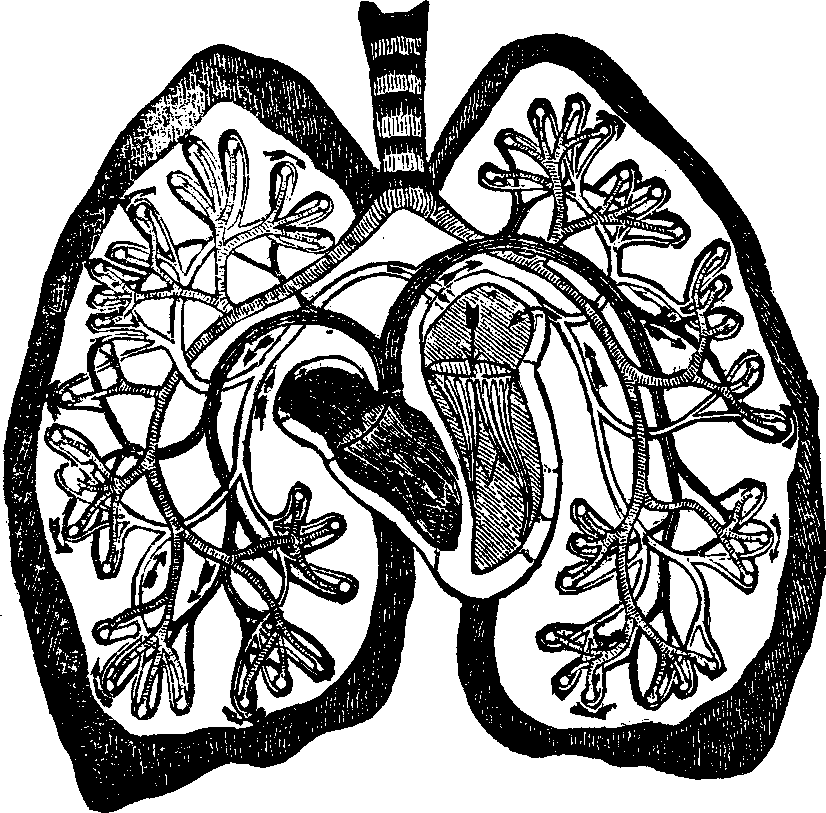

substance, and the arrangement of the pigmentary matter. C.

Transverse sections, showing the distinction between the cortical and

medullary substances, and the central collection of pigmentary matter,

sometimes found in the latter. Magnified 310 diameters.

Hairs are horny appendages of the skin, and, with the exception

of the hands, the soles of the feet, the backs of the fingers and toes,

between the last joint and the nail, and the upper eyelids, are distributed

more or less abundantly over every part of the surface of the body. Over

the greater part of the surface the hairs are very minute, and in some

places are not actually apparent above the level of the skin; but the hair

of the head, when permitted to reach its full growth, attains a length of

from twenty inches to a yard, and, in rare instances, even six feet. A hair